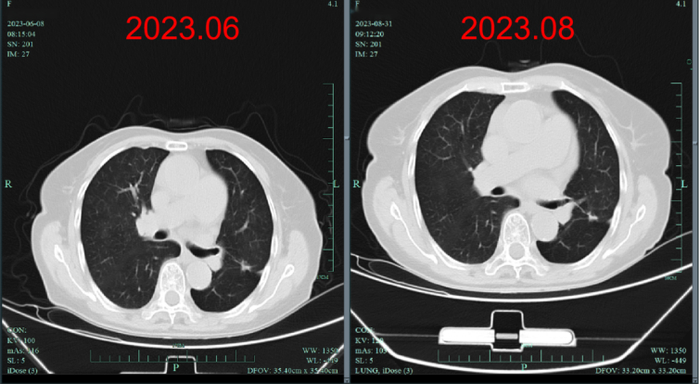

疗效评估:复查时原发灶较基线时明显缩小,达到深度缓解,并在随后治疗中持续缓解长达39个月。

上述病例为初诊转移性NSCLC患者,在基因检测明确BRAF V600E突变后,接受达拉非尼+曲美替尼一线治疗。在服药1月余后复查肺部CT,原发灶较基线时明显缩小,疗效评价达到深度缓解。截至2023年11月最后一次随访,该患者已获得长达39个月的PFS。该病例的治疗过程再次印证了达拉非尼+曲美替尼一线治疗的长生存获益。